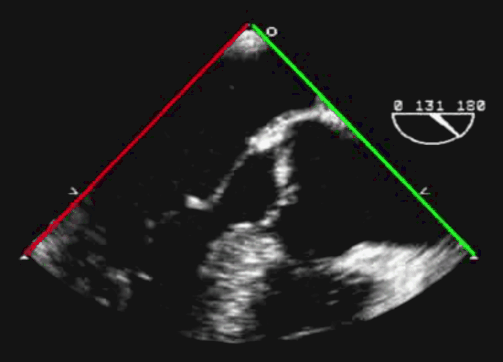

食管中段左室长轴切面(LAX view)

超声探头位置与前述两腔心切面时一致、位于左心房后部,旋转晶片角度至 130° 左右(图 14)。可在长轴方向显示主动脉瓣和左室流出道,调整超声探头深度使得整个左心室在图像中显示。左心室前间膈和下侧壁、二尖瓣 A2 及 P2 均能清晰显示(图 15)。

该切面用于诊断二尖瓣、主动脉瓣、主动脉根部和室间隔病变,也可用于评估左室功能。此切面也是二尖瓣缘对缘修复术(TEER)中的重要参考依据。

另有两个基本切面与左室长轴切面存在联系:即左室流出道切面(LVOT view)以及主动脉瓣长轴切面(AV LAX view)。

前者与左室长轴切面基本相同。而后者相较于左室长轴切面,超声探查深度更浅,图像关注点主要在于流出道及主动脉根部,左室及二尖瓣仅显示部分(图 16)。